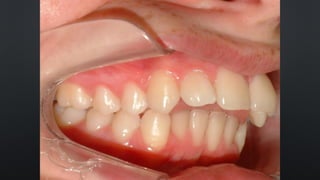

• OVERBITE OU SOBREMORDIDA

RELAÇÃO ENTRE ARCOS

TRESPASSE VERTICAL

• REFERE-SE AO QUANTO OS INCISIVOS SUPERIORES COBREM NOS INFERIORES

• APROXIMADAMENTE 30%

• OVERJET OU SOBRESALIÊNCIA

TRESPASSE HORIZONTAL

• REFERE-SE AO DISTANCIAMENTO ENTRE OS INCISIVOS SUPERIORES E INFERIORES

• NORMALMENTE 2MM

• OVERBITE OUSOBREMORDIDA RELAÇÃO ENTRE ARCOS TRESPASSE VERTICAL • REFERE-SE AO QUANTO OS INCISIVOS SUPERIORES COBREM NOS INFERIORES • APROXIMADAMENTE 30%

• OVERJET OUSOBRESALIÊNCIA RELAÇÃO ENTRE ARCOS TRESPASSE HORIZONTAL • REFERE-SE AO DISTANCIAMENTO ENTRE OS INCISIVOS SUPERIORES E INFERIORES • NORMALMENTE 2MM